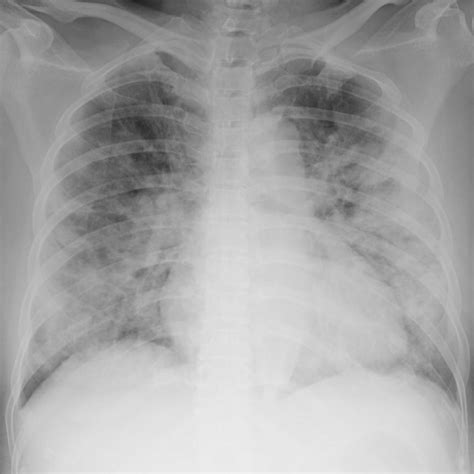

During the program, participants will receive lectures on the imaging features of pneumoconiosis and the international labor organization (ilo. Web the b reader program aims to ensure competency in radiographic reading by evaluating the ability of readers to classify a test set of radiographs, thereby creating and maintaining a pool of qualified readers having the skills and ability to. Web the acr education center has committed to providing at least two courses, including training and examination, to qualify at least 80 physicians to become certified b readers by august 2020. Listing does not imply medical licensure. To read black lung screening exams. National institute for occupational safety and health (niosh) has selected the american college of radiology (acr) education center to provide training to increase the number of b readers available in the u.s. Physicians from inside the united states that have who have demonstrated competence in applying the ilo classification by successfully completing the niosh b reader examination within the last 4 years. We summarize trends in participation and examinee attributes and performance during 1987 to 2018. Web the national institute for occupational safety and health (niosh) b reader program provides the opportunity for physicians to demonstrate proficiency in the international labour office (ilo) system for classifying radiographs of pneumoconioses. Read the bulletin » read the jacr

During the program, participants will receive lectures on the imaging features of pneumoconiosis and the international labor organization (ilo. Web the b reader program aims to ensure competency in radiographic reading by evaluating the ability of readers to classify a test set of radiographs, thereby creating and maintaining a pool of qualified readers having the skills and ability to. During the program, participants will receive lectures on the imaging features of pneumoconiosis and the international labor organization (ilo. Web learn more about the niosh b reader program and how to become a b reader. We summarize trends in participation and examinee attributes and performance during 1987 to 2018. Physicians from inside the united states that have who have demonstrated competence in applying the ilo classification by successfully completing the niosh b reader examination within the last 4 years. National institute for occupational safety and health (niosh) has selected the american college of radiology (acr) education center to provide training to increase the number of b readers available in the u.s. Web the jacr and acr bulletin provide topics relevant to the practice of radiology and information about the college's services and members. To read black lung screening exams. Web the national institute for occupational safety and health (niosh) b reader program provides the opportunity for physicians to demonstrate proficiency in the international labour office (ilo) system for classifying radiographs of pneumoconioses. Web the acr education center has committed to providing at least two courses, including training and examination, to qualify at least 80 physicians to become certified b readers by august 2020.